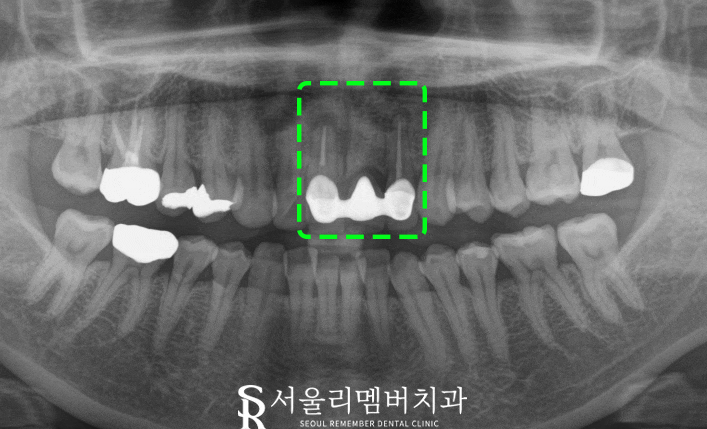

x-ray 사진을 찍어보니

예전 치료했던 보철 하방으로

치조골이 퇴축하였고

뿌리 끝 쪽을 보면 염증이 가득한걸

확인할 수 있습니다.